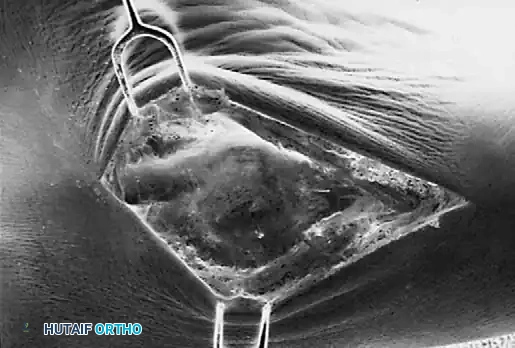

Advanced Imaging and Anatomical Reference Gallery

The following images illustrate various presentations, surgical exposures, and advanced imaging modalities (including CT and MRI correlates) utilized in the comprehensive evaluation and treatment of rigid pes planus and tarsal coalitions: